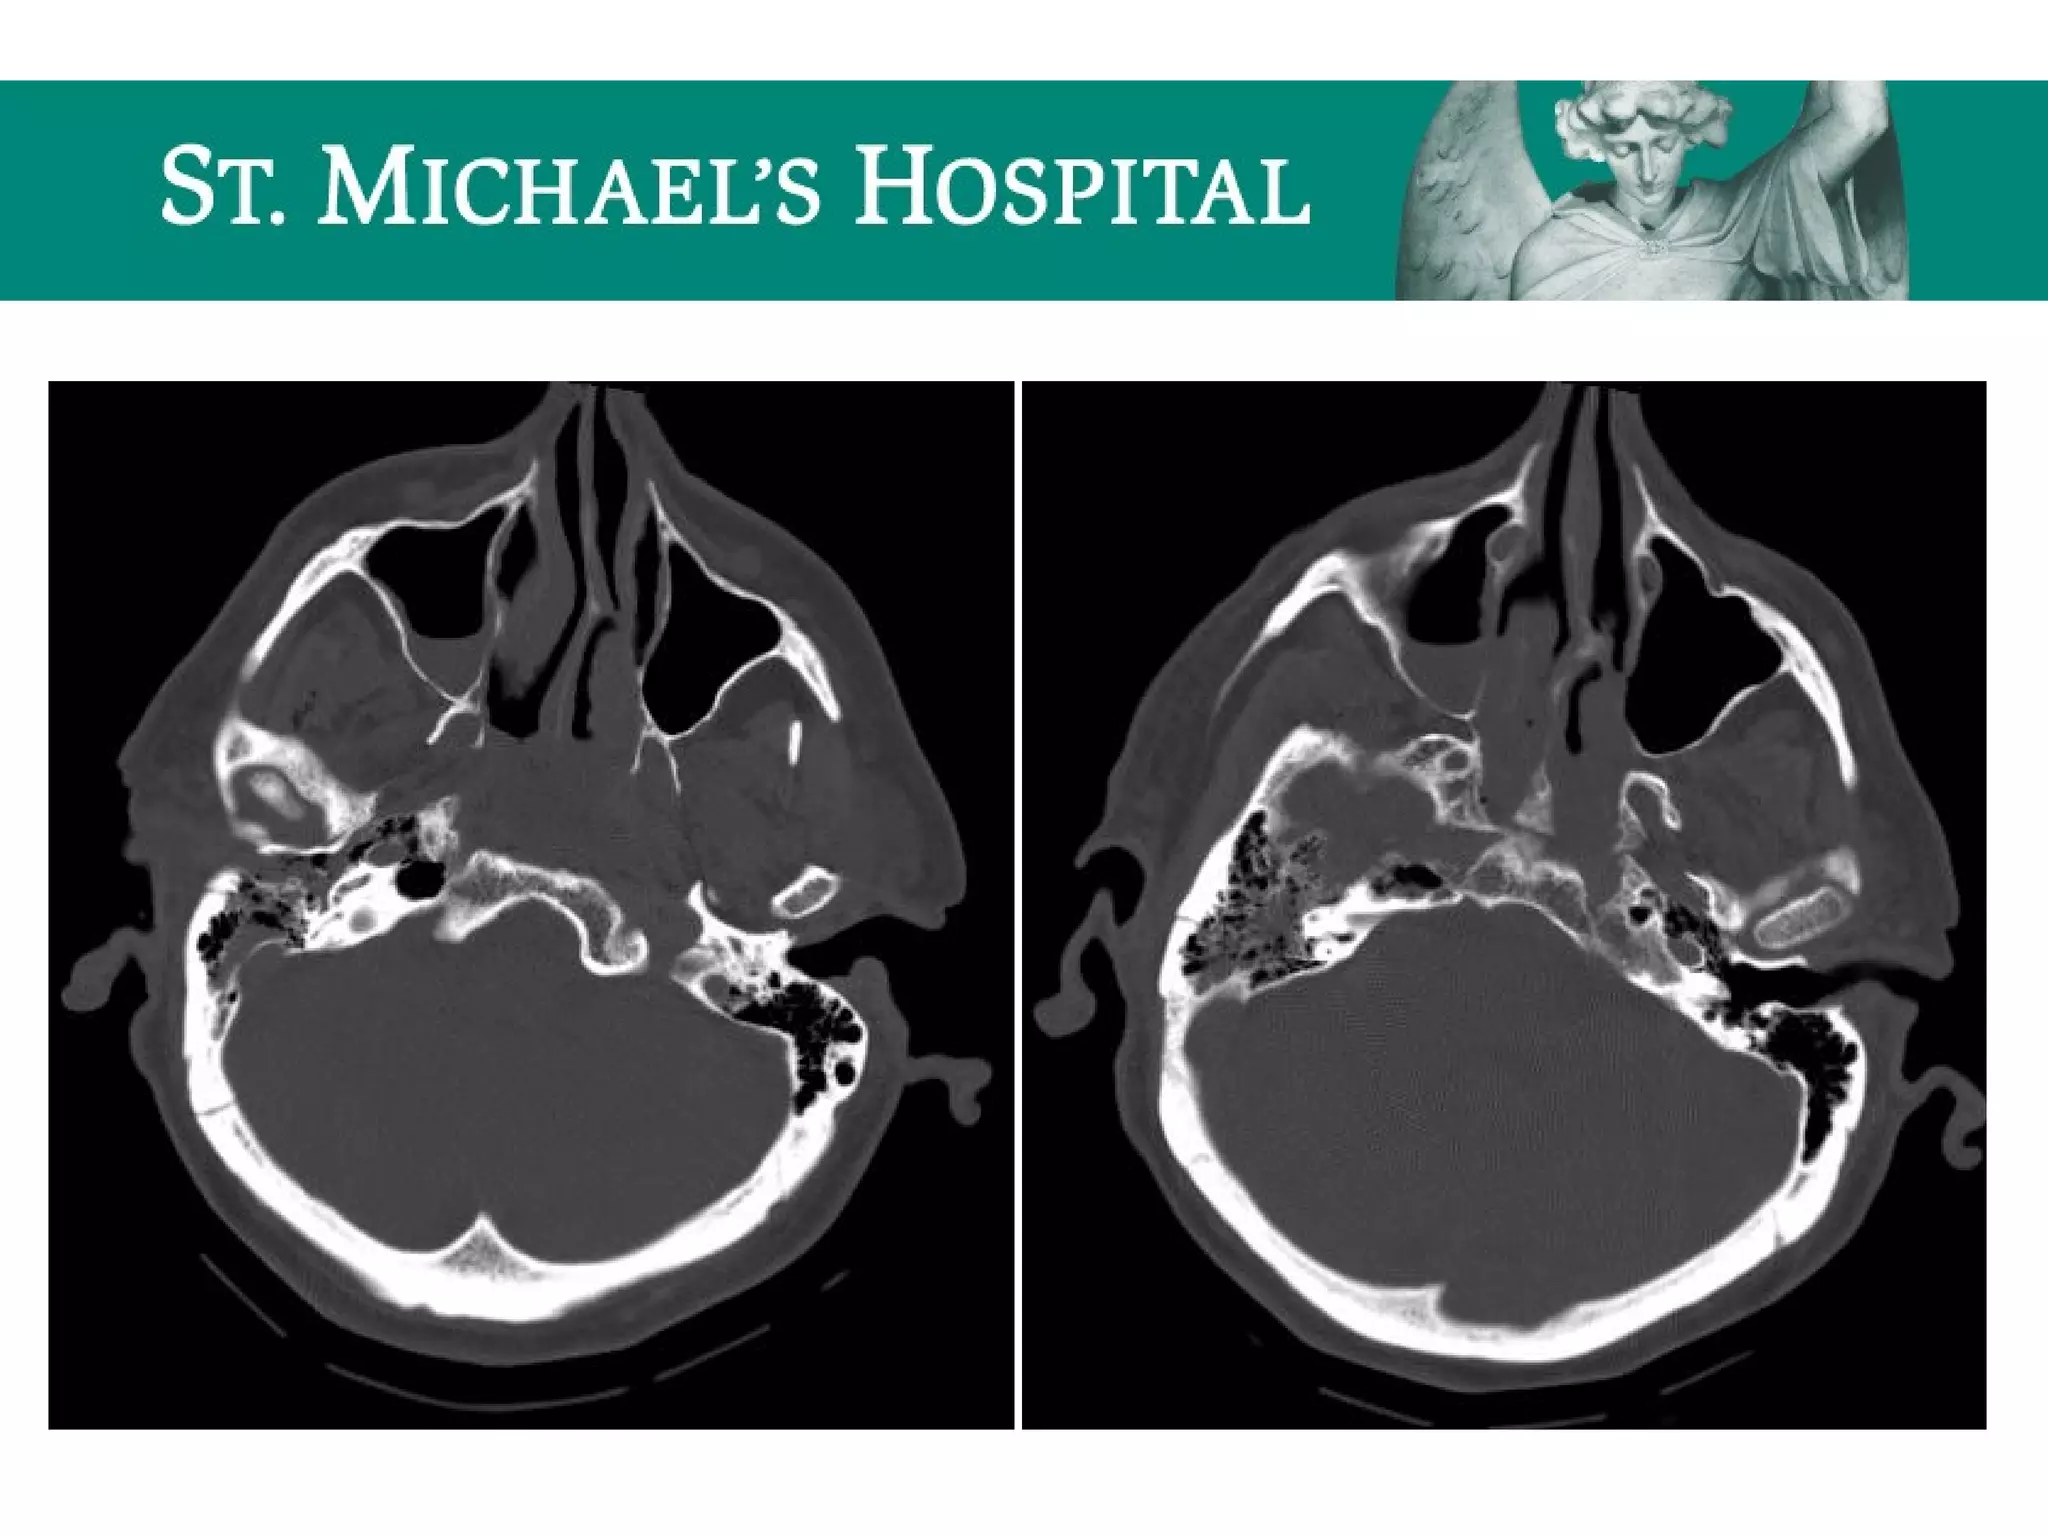

Unenhanced CT – Bone Window

 Paranasal sinuses

 Frontal, ethmoid, maxillary, sphenoid opacification

 Subcutaneous/orbital emphysema/pneumocephalus

 Mastoid air cells

 Opacification

 Hemotympanum

 Subcutaneous emphysema/pneumocephalus

 Bones (fractures)

 Facial  nasal bone, bony orbit, bony sinuses, mandible

 Skull base  petrous temporal bone fractures (longitudinal vs. transverse)

 Calvarium  linear vs. depressed

 Occipital condyles

Unenhanced CT –Bone Window  Paranasal sinuses  Frontal, ethmoid, maxillary, sphenoid opacification  Subcutaneous/orbital emphysema/pneumocephalus  Mastoid air cells  Opacification  Hemotympanum  Subcutaneous emphysema/pneumocephalus  Bones (fractures)  Facial  nasal bone, bony orbit, bony sinuses, mandible  Skull base  petrous temporal bone fractures (longitudinal vs. transverse)  Calvarium  linear vs. depressed  Occipital condyles